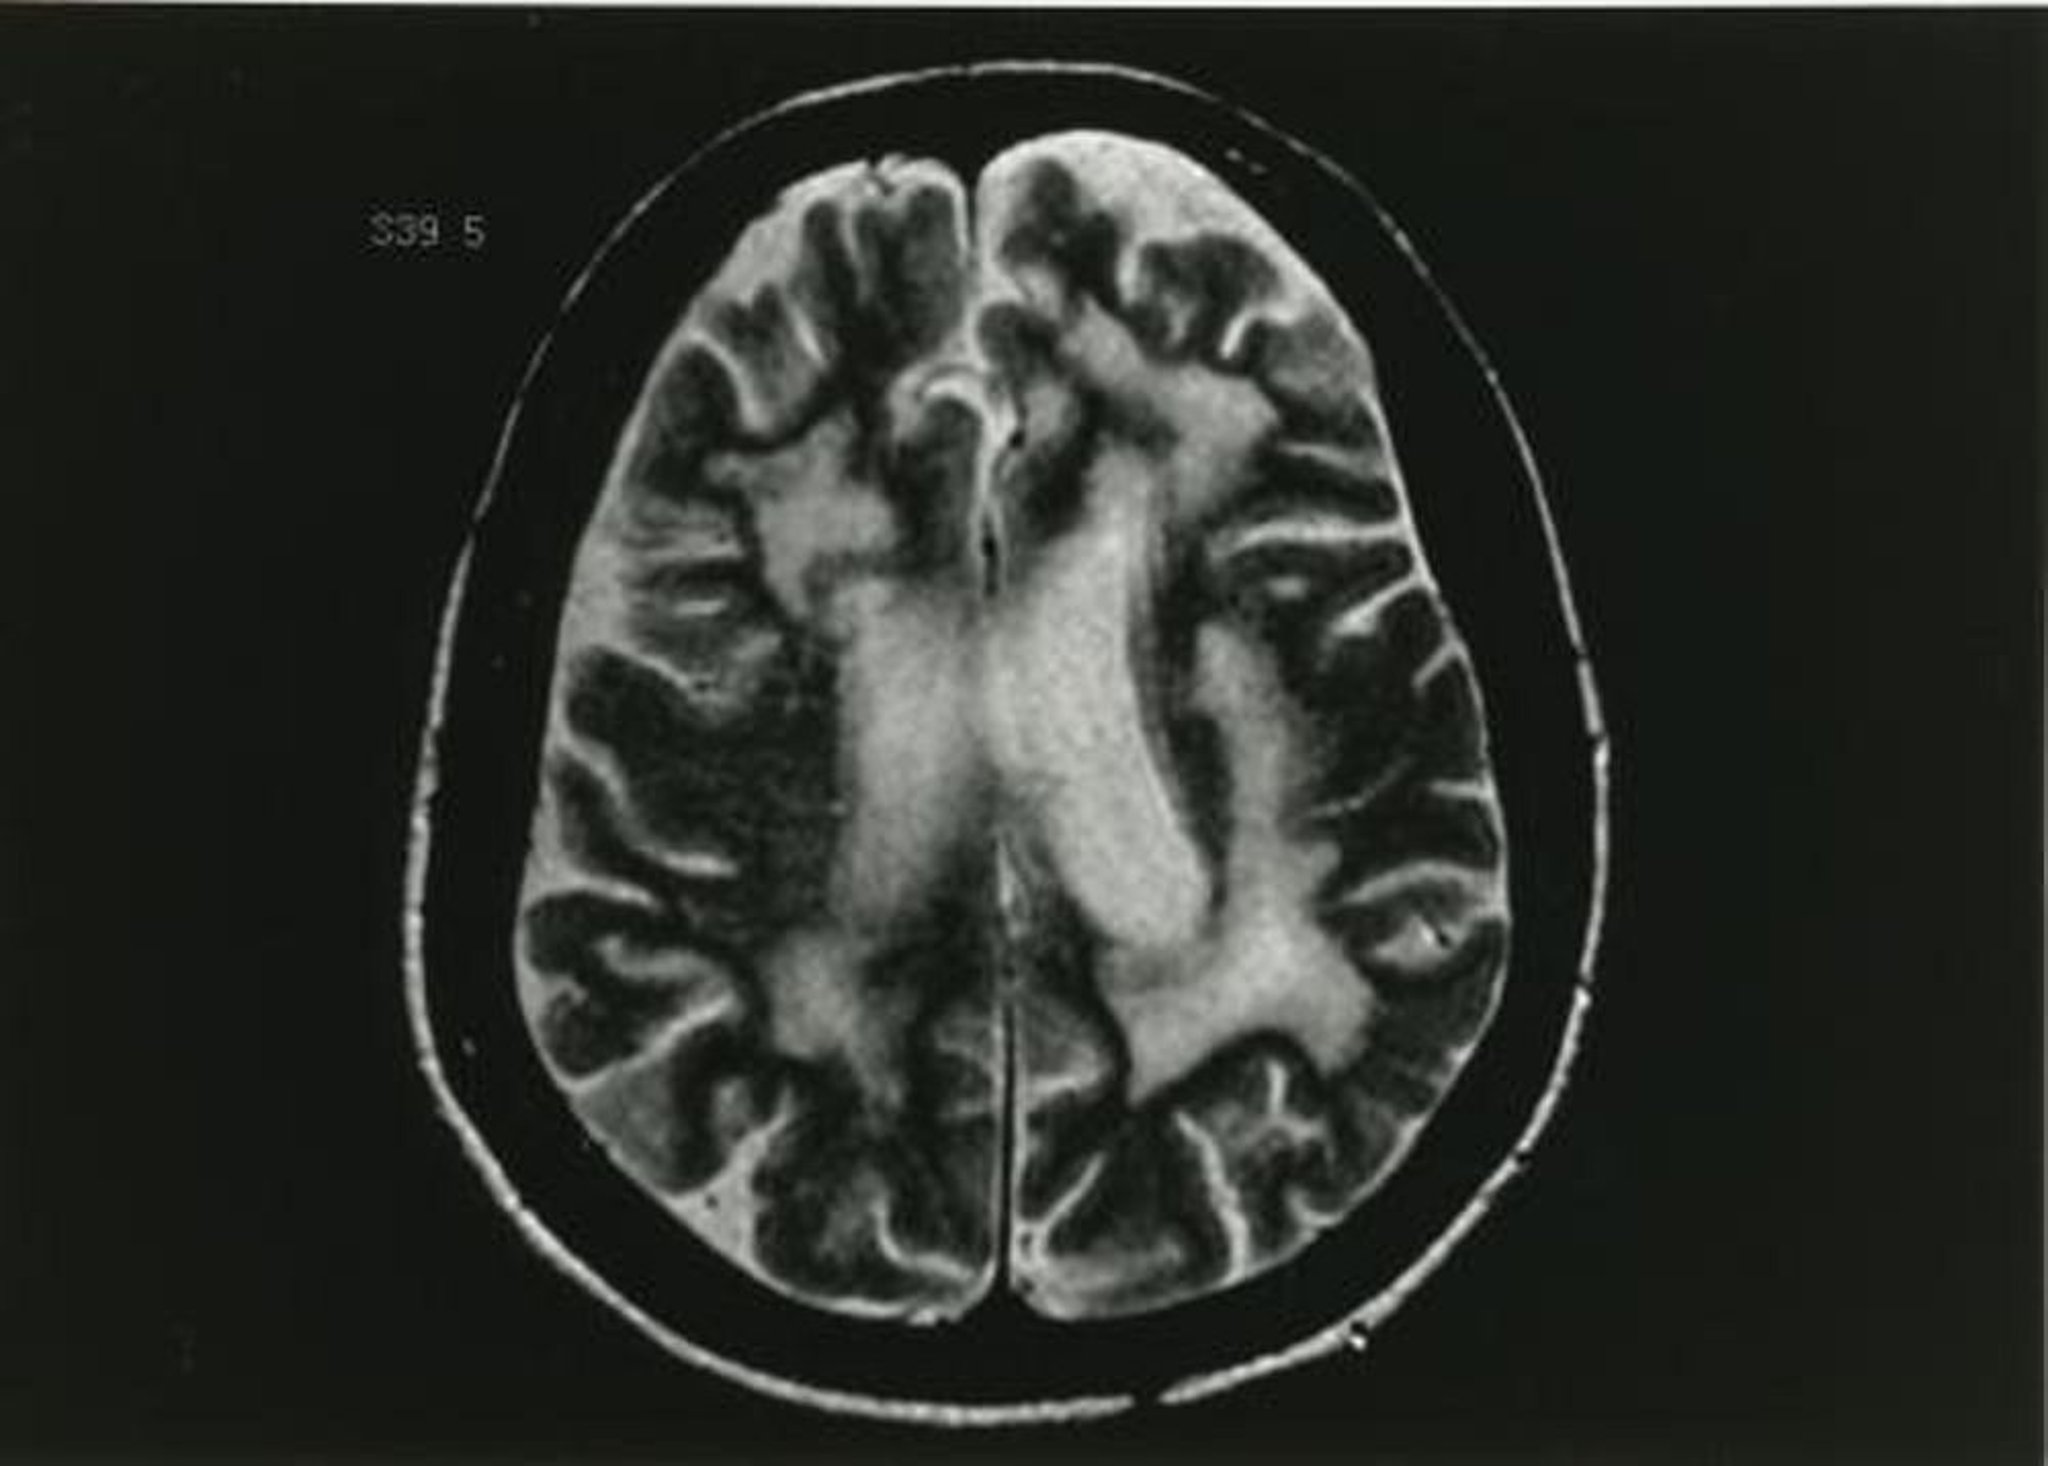

Essa imagem de RM ponderada em T2 mostra múltiplas áreas de alteração da substância branca.

Imagem fornecida por John E. Greenlee, MD.